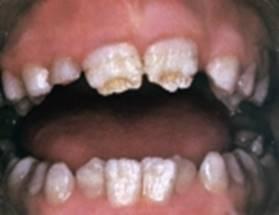

Клинически различают три формы системной гипоплазии:

Изменение цвета

Слабая степень недо-развития эмали проявляется в виде пятен чаще белого, реже желтоватого цвета, с четкими границами и одинаковой величины на одноименных зубах. Пятна обычно обнаруживаются на вестибулярной поверхности и не сопровождаются какими-либо неприятными ощущениями. Пятна при гипоплазии не окрашиваются красителями (в отличие от кариеса в стадии пятна).

Недоразвитие

Более тяжёлой формой гипоплазии эмали является ее недоразвитие, которая прояв-ляется по разному (волнистая, точечная, бороздчатая эмаль). На поверхности эмали обнаружи-ваются углубления или бороздки. Эмаль в углублениях остается плотной и гладкой.

Отсутствие эмали

Наиболее редко встречающейся формой гипоплазии является ее отсуствие (аплазия) на определенном участке. При этой форме могут быть жалобы на болевые ощущения от термических и химических раздражителей.

Пятна, бороздки и гнезда

Как уже говорилось, основным клиническим проявлением гипоплазии является изменение внешнего вида зуба. Существует несколько форм поражения. Гипоплазия может проявляться в виде белых пятен (пятнистая форма), чашеобразных углублений округлой формы (эрозивная форма), в виде одиночных или множественных бороздок (бороздчатая и волнистая форма).

Свидетельством тяжелого поражения является полное отсутствие эмали, называемое аплазией. Появление апластической формы является следствием грубых нарушений развития зуба и обычно сочетается с другими пороками развития.

По классификации проф. В. К. Патрикеева, различают: следующие формы системной гипоплазии эмали: Пятнистую, чашеобразную, бороздчатую и аплазию. Длят всех форм гипоплазии эмали характерны поражение группы зубов одного периода минерализации, расположение дефекта строго по одной линии ближе к режущему краю на всей группе зубов, четкие края, гладкая блестящая поверхность дна и стенок дефекта.

Пятнистая форма гипоплазии эмали проявляется гладкими белыми пятнами с четкими контурами. Эта форма указывает на недостаточное обызвествление эмали при законченном ее формировании. Чашеобразная форма имеет вид овальных или округлых углублений с гладкими стенками и дном. Бороздчатая форма гипоплазии проявляется бороздками различной глубины и ширины с четкими ровными краями, с гладким блестящим дном и стенками. Аплазия, т. е. полное отсутствие эмали на дне дефекта - наиболее, тяжелое поражение.